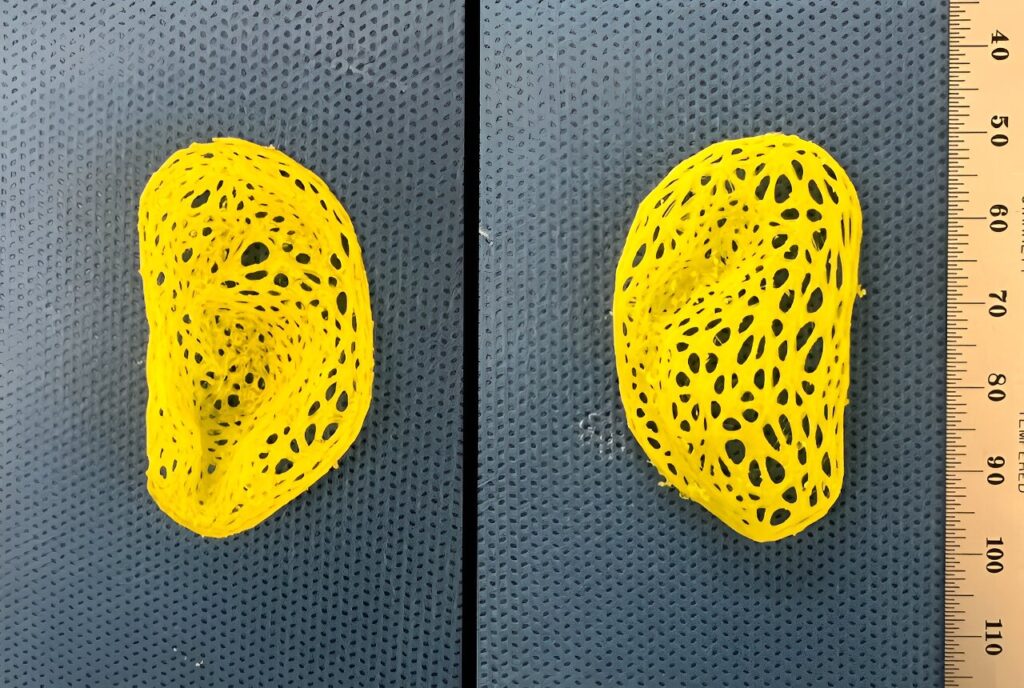

Για την αντιμετώπιση αυτού του προβλήματος, ο Δρ. Σπέκτορ και η ομάδα του χρησιμοποίησαν αποστειρωμένο χόνδρο από ζώα ο οποίος είχε τροποποιηθεί έτσι ώστε να μην προκαλέσει απόρριψη του μοσχεύματος. Στη συνέχεια τοποθέτησαν τον χόνδρο σε περίπλοκα πλαστικά ικριώματα σε σχήμα αυτιού τα οποία δημιούργησαν με τη βοήθεια ενός τρισδιάστατου εκτυπωτή. Τα μικρά κομμάτια χόνδρου λειτουργούν ως εσωτερικές ενισχύσεις για να προκαλέσουν σχηματισμό νέου ιστού μέσα στο ικρίωμα. Τους επόμενους τρεις έως έξι μήνες, η δομή αναπτύχθηκε σε χόνδρο που περιείχε ιστό ο οποίος αναπαρήγαγε τα ανατομικά χαρακτηριστικά του αυτιού.

Για να ελέγξουν την αίσθηση του αυτιού, οι ερευνητές πραγματοποίησαν εμβιομηχανικές μελέτες οι οποίες επιβεβαίωσαν ότι το αντίγραφο διέθετε παρόμοια ευελιξία και ελαστικότητα με τον χόνδρο του ανθρώπινου αυτιού. Ωστόσο, το κατασκευασμένο υλικό δεν ήταν τόσο ισχυρό όσο ο φυσικός χόνδρος και μπορούσε να σκιστεί. Για να λύσει αυτό το πρόβλημα, ο Δρ, Σπέκτορ σχεδιάζει να προσθέσει χονδροκύτταρα στο μείγμα, τα οποία θα προέρχονται από ένα μικρό κομμάτι χόνδρου από το άλλο αυτί του παραλήπτη. Αυτά τα κύτταρα θα αποθέσουν τις ελαστικές πρωτεΐνες που κάνουν τον χόνδρο του αυτιού τόσο εύρωστο, δημιουργώντας ένα μόσχευμα που θα είναι εμβιομηχανικά παρόμοιο με το εγγενές αυτί, κατέληξε ο ερευνητής.